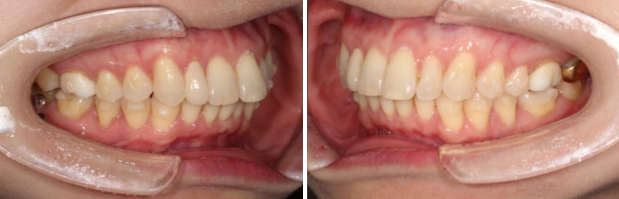

좌 - 치료 전 / 우 - 치료 후

24.02~24.12

치간삭제를 통한 앞니 돌출감 개선

앞니 배열 개선과 가위교합 개선

쓰러진 큰 어금니는 잘 세웠습니다.

치간삭제를 통한 아래 앞니 배열의 개선

과개교합과 중심선의 개선